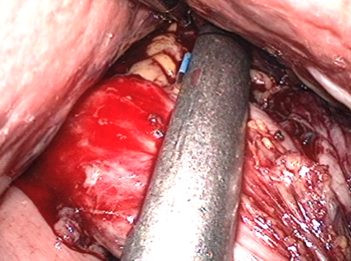

この段階で十二指腸を切り離します。

ホチキス付カッターで一気に切り離します。